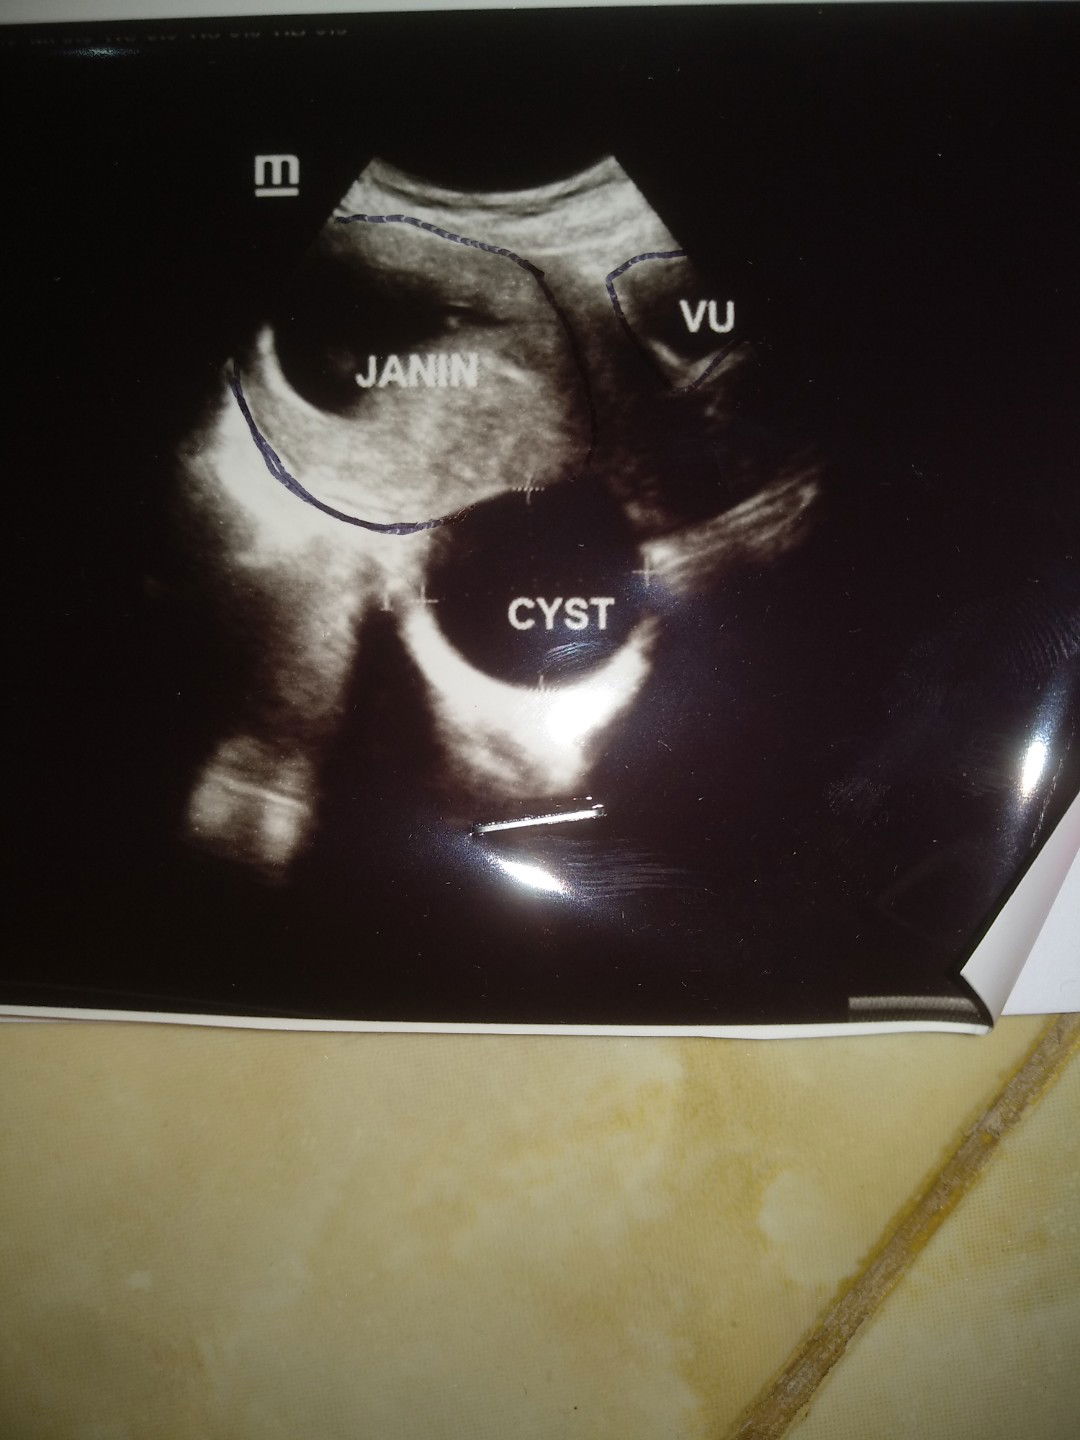

kista saat hamil

Bun, sy hamil 11 minggu, td mlm check k dokter, pas usg,dktr ny nanya, ibu ad kista ya? Sy kaget blm smpt jwb, dktr ny jlasin ltak kista nya, bntuknya bulat, ukuran 4x 3,9 cm kt ny.sy smpt shock, krna gk ngeh klo ad kista.smpe gak fokus ke baby nya, tp baby nya alhamdulillah sehat. Trus sy tnya, ap pemicu tmbulnya kista? Kt dokter ny bs dr pola makan, srg mkan yg pke pnyedap,pwrna,pngawet, atau bs jg krna prnh kb hormonal. Kbtlan sy dlu kb suntik, kt dktr, klo sdh ad riwayat kista gini, gk blh lg kb hormonal, bs ny iud..jd sy dsaranin makan gk ush pke msg,, pnydap sprti masako jg gk blh.. Ktnya pas hamil ad kista itu bs mngncam kguguran, sy dsaranin check up sblan skli dan pantau ukrn kista nya..biasanya klo khmilan mkin bsar kista ny nnti kalah sndri.. klo lahiran nnti normal d observasi lg kista ny msh ad gk stlh mlahirkan, klo caesar, bs langsung d angkat, trus dokter ny blg klo d angkat nnti jd ny indung telur sy tgl 1, sy kaget, jd gmn dok, msh bs hamil lg gk klo d angkat 1, kt ny bisa..kn msh ad satu lg, tp sy shock smpe gemeteran semua kaki, bunda dsini ad yg pny pnglman yg sama gak? Sy dresepin ultrageston, tp blm sy tebus, klo ad yg pny pnglman sama share ya bun? Sy takut gk bs lahiran normal gr2 kista..